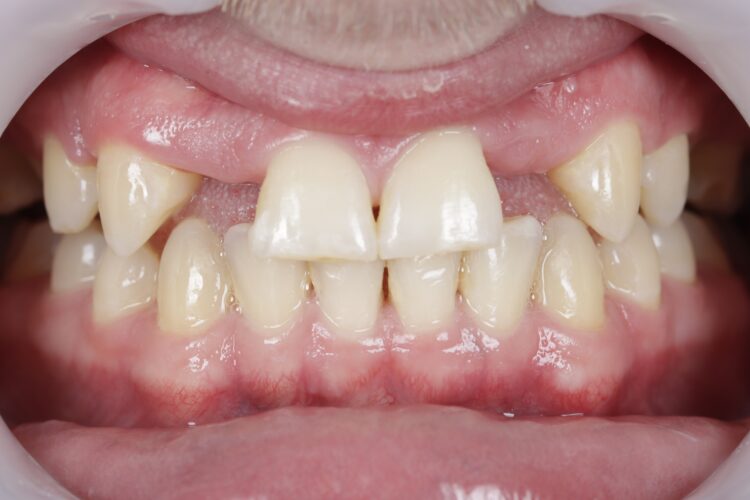

Hypodontia is a developmental condition in which one or more teeth fail to develop. This case report details the dental implant rehabilitation of a 26-year-old male patient with hypodontia who was missing multiple teeth and underwent orthodontic treatment followed by implant placement in the lateral incisor regions. The case was also showcased during a live surgical demonstration, highlighting its clinical and aesthetic challenges.

The patient, now 27, presented with multiple missing teeth due to congenital hypodontia. He was missing four teeth in the upper jaw, particularly the lateral incisors. The patient had undergone orthodontic treatment before implant placement to optimise the spacing for the implants in the upper right two (UR2) and upper left two (UL2) regions.

The orthodontist moved the patient’s teeth into an ideal position, ensuring proper alignment and sufficient space for the implants in the lateral incisor regions. This process took five years, due to the COVID-19 pandemic and the patient’s work commitments, during which time the braces were reviewed and adjusted as necessary.